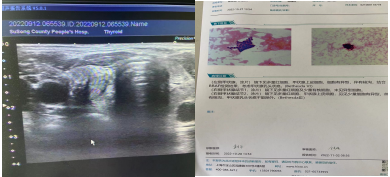

甲状腺针吸细胞学活检 细胞学结果

(五)超声引导下亚急性甲状腺炎局部精准注射治疗